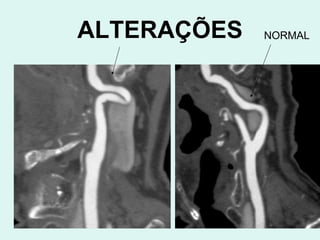

ALTERAÇÕES NORMAL

VERTEBRAIS NORMAIS